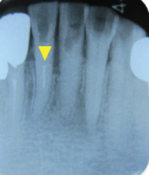

症例(マイクロスコープを用いた歯の根の治療:破折ファイルの除去)